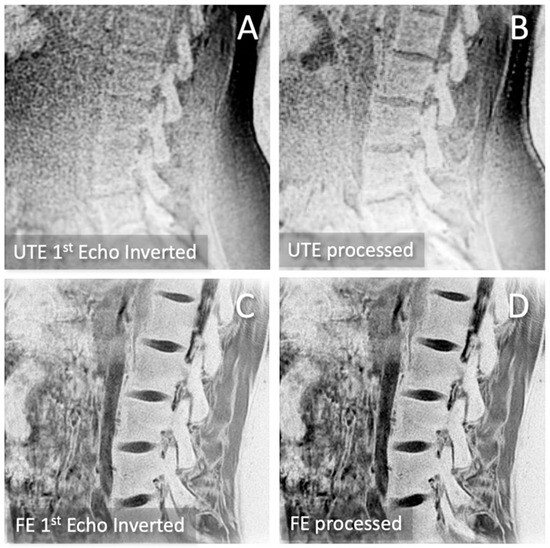

2.3. CT-like Image Processing

3.1. Observations